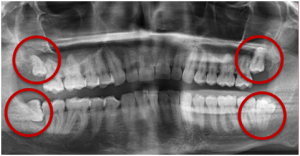

- Removal of one or more wisdom teeth